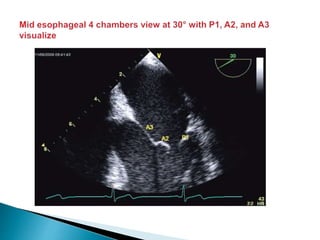

 The posterior leaflet has clefts that divide it into 3 scallops (P1, P2, and P3);

 The anterior leaflet has no such scallops, but is described as having three regions that reflect

those of the posterior leaflet (A1, A2, and A3 respectively).

 In addition to the points of apposition along the leaflets, there are anterior (adjacent to A1/P1)

and posterior (adjacent to A3/P3) commissures.